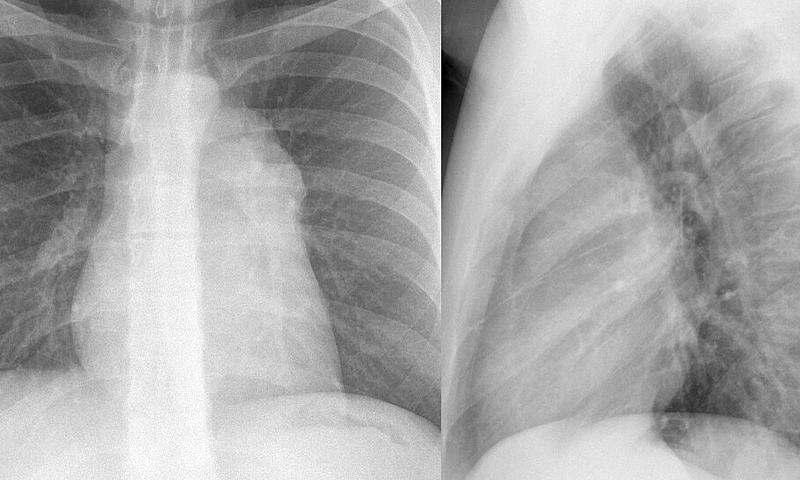

Case 1c

Thymoma